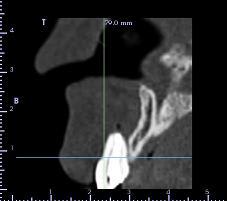

pour la 21, çà va...mais la 11 est à bout de souffle...avec l'apex qui traverse la gencive vestibulaire...

veut un implant...forcément...mais là, faut une greffe...plutôt importante...

bon, autre truc plutôt défavorable au greffon ramique...je viens de vérifier: contact des apex de 38 et 48 avec le NDI...et comme les dds ont suffisamment de place...on laisse tranquillement évoluer...

Sinon concernant ton cas j'ai l'impression qu'il y a de l'os en mesial et distal de ta dent du coup si c'est bien le cas je ferais de la rog avec une membrane pinsee